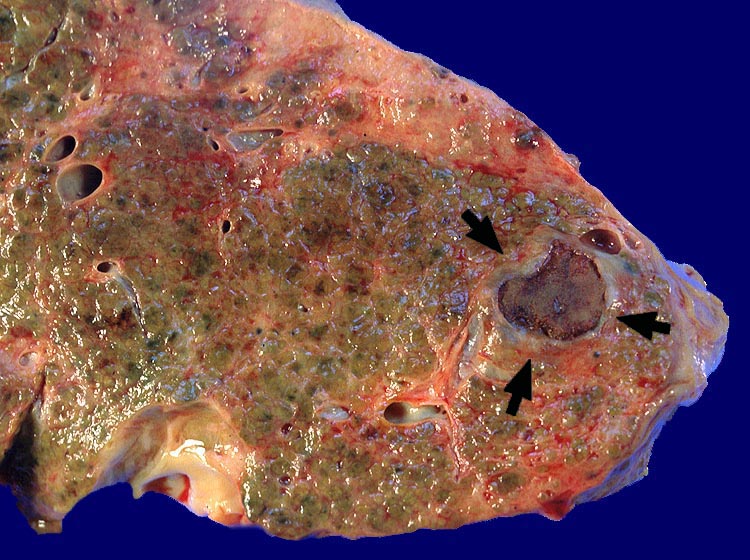

PathoPic ID 1192 - nekrotisches Hepatozelluläres Karzinom geheilt durch Alkoholinjektion

nekrotisches Hepatozelluläres Karzinom geheilt durch Alkoholinjektion

Fibrös abgekapseltes vollständig nekrotisches hepatozelluläres

Karzinom. Feinknotiger zirrhotischer Umbau.

Zirrhose bei chronischer Hepatitis C und Alkoholabusus. St.n. Alkoholinjektion in einen solitären Herd eines hepatozellulären Karzinoms vor 3 Jahren.